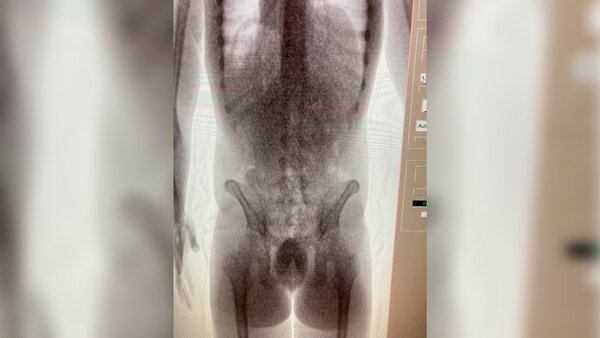

Telegram / ФТС России | ProТаможню

"25-летнего мужчину вычислили в ходе оперативных мероприятий. Он доставлял в Россию партию "жидкого" кокаина из Бразилии за денежное вознаграждение в 300 тысяч рублей. Наркотик находился в 32 контейнерах, сокрытых в его желудочно-кишечном тракте", — сказано в сообщении ведомства.